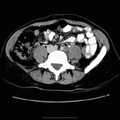

RADIOLOGY: ABDOMEN: Case# 33001: DUPLICATED OBSTRUCTED KIDNEY, STENT LOWER POLE. 41-year-old white female with malignant melanoma of the left knee with metastases to the inguinal lymph nodes. The patient is status post lymph node dissection. 1. 2.0 x 1.0 cm left para-aortic lymph node is minimally decreased in size from the prior examination; the change is probably not significant. This lymph node was successfully biopsied using CT guidance. 2. 1.0 cm low attenuation lesion in right hepatic lobe is unchanged since the previous examination. The lesion is too small to characterize. 3. Duplicated left urinary collecting system. A stent is seen in the left ureter with decreased enhancement of the superior and posterior aspects of the left kidney. The stent and decreased enhancement are new since the prior examination. There is duplication of the collecting system with stenting of the inferior moiety only. 4. A 1.0 x 1.2 cm low attenuation area is seen in the region of the left psoas muscle and is of uncertain significance. 5. Post-surgical changes in the left groin. 6. Prominence of the left adnexa which is unchanged since the prior examination. 7. No evidence of pulmonary metastases.